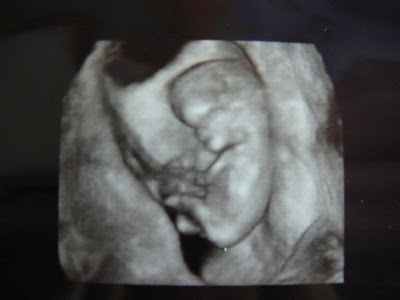

This is my last son at 6 weeks. There is a heart beat

7 weeks

8 weeks

9 weeks

10 weeks

11 weeks